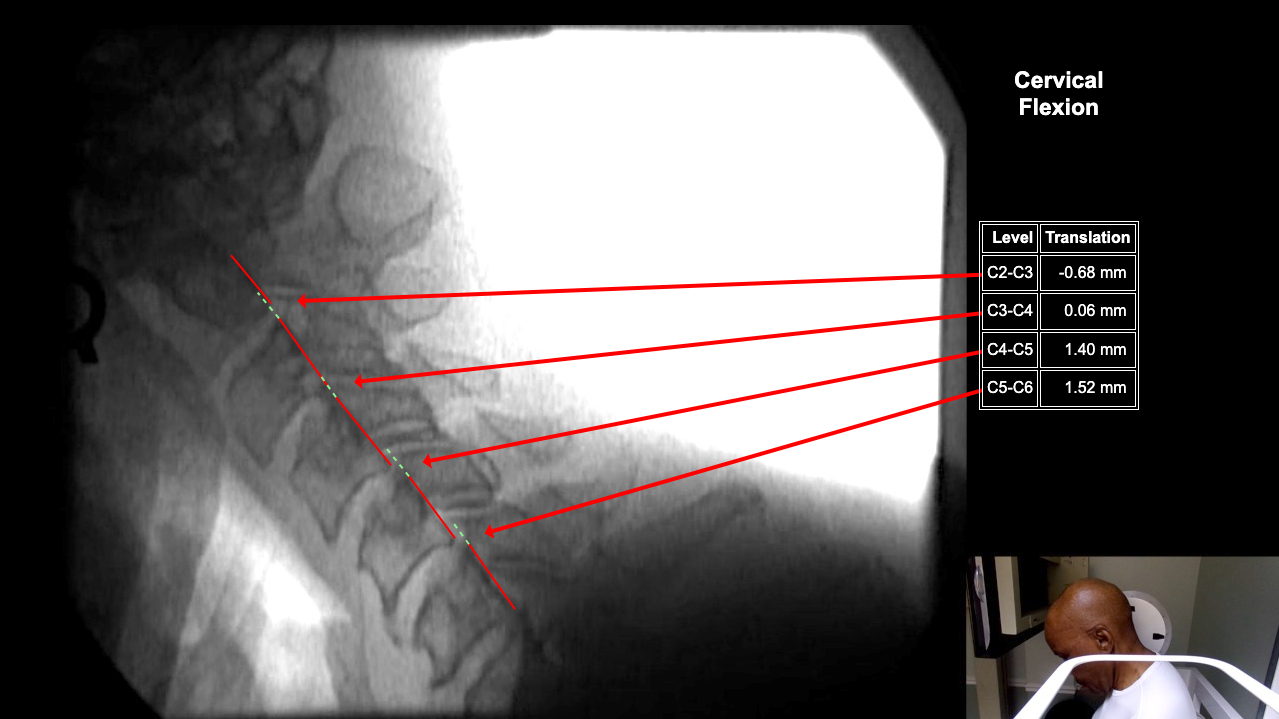

Home > Frederick Littlefield DMX 1-20-26